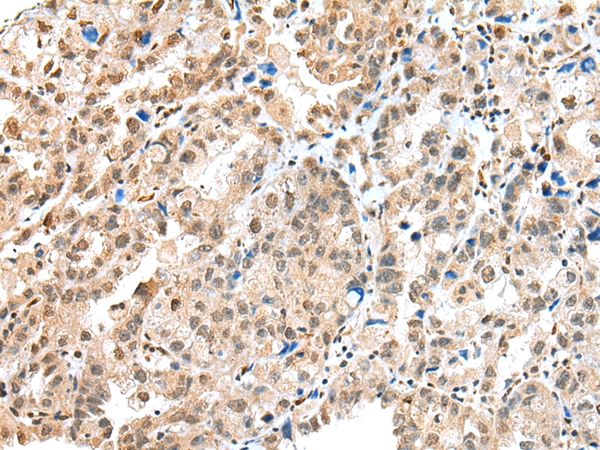

Immunohistochemical analysis of paraffin-embedded Human prostate cancer tissue using #42896 at dilution 1/25.

Immunohistochemical analysis of paraffin-embedded Human ovarian cancer tissue using #42896 at dilution 1/25.